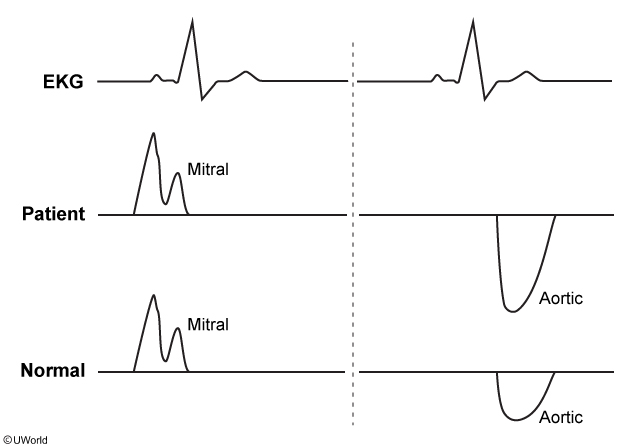

A 63-year-old man comes to the office due to shortness of breath on exertion over the last 6 months. The patient describes his symptoms as progressive, causing him to decrease his outside activities recently. He has no dyspnea at rest. During evaluation, Doppler flow tracings across his aortic and mitral valves are acquired from an apical window. The patient’s ECG and flow velocity tracings are presented above normal tracings in the exhibit below.

This patient most likely suffers from which of the following?